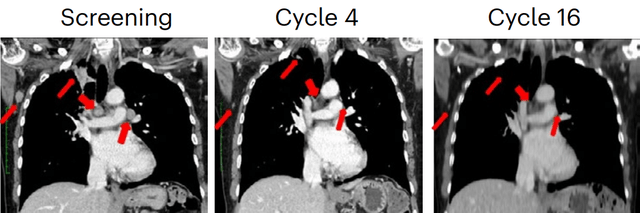

一名三阴性乳腺癌患者肺转移病灶也得到明显的缩小。